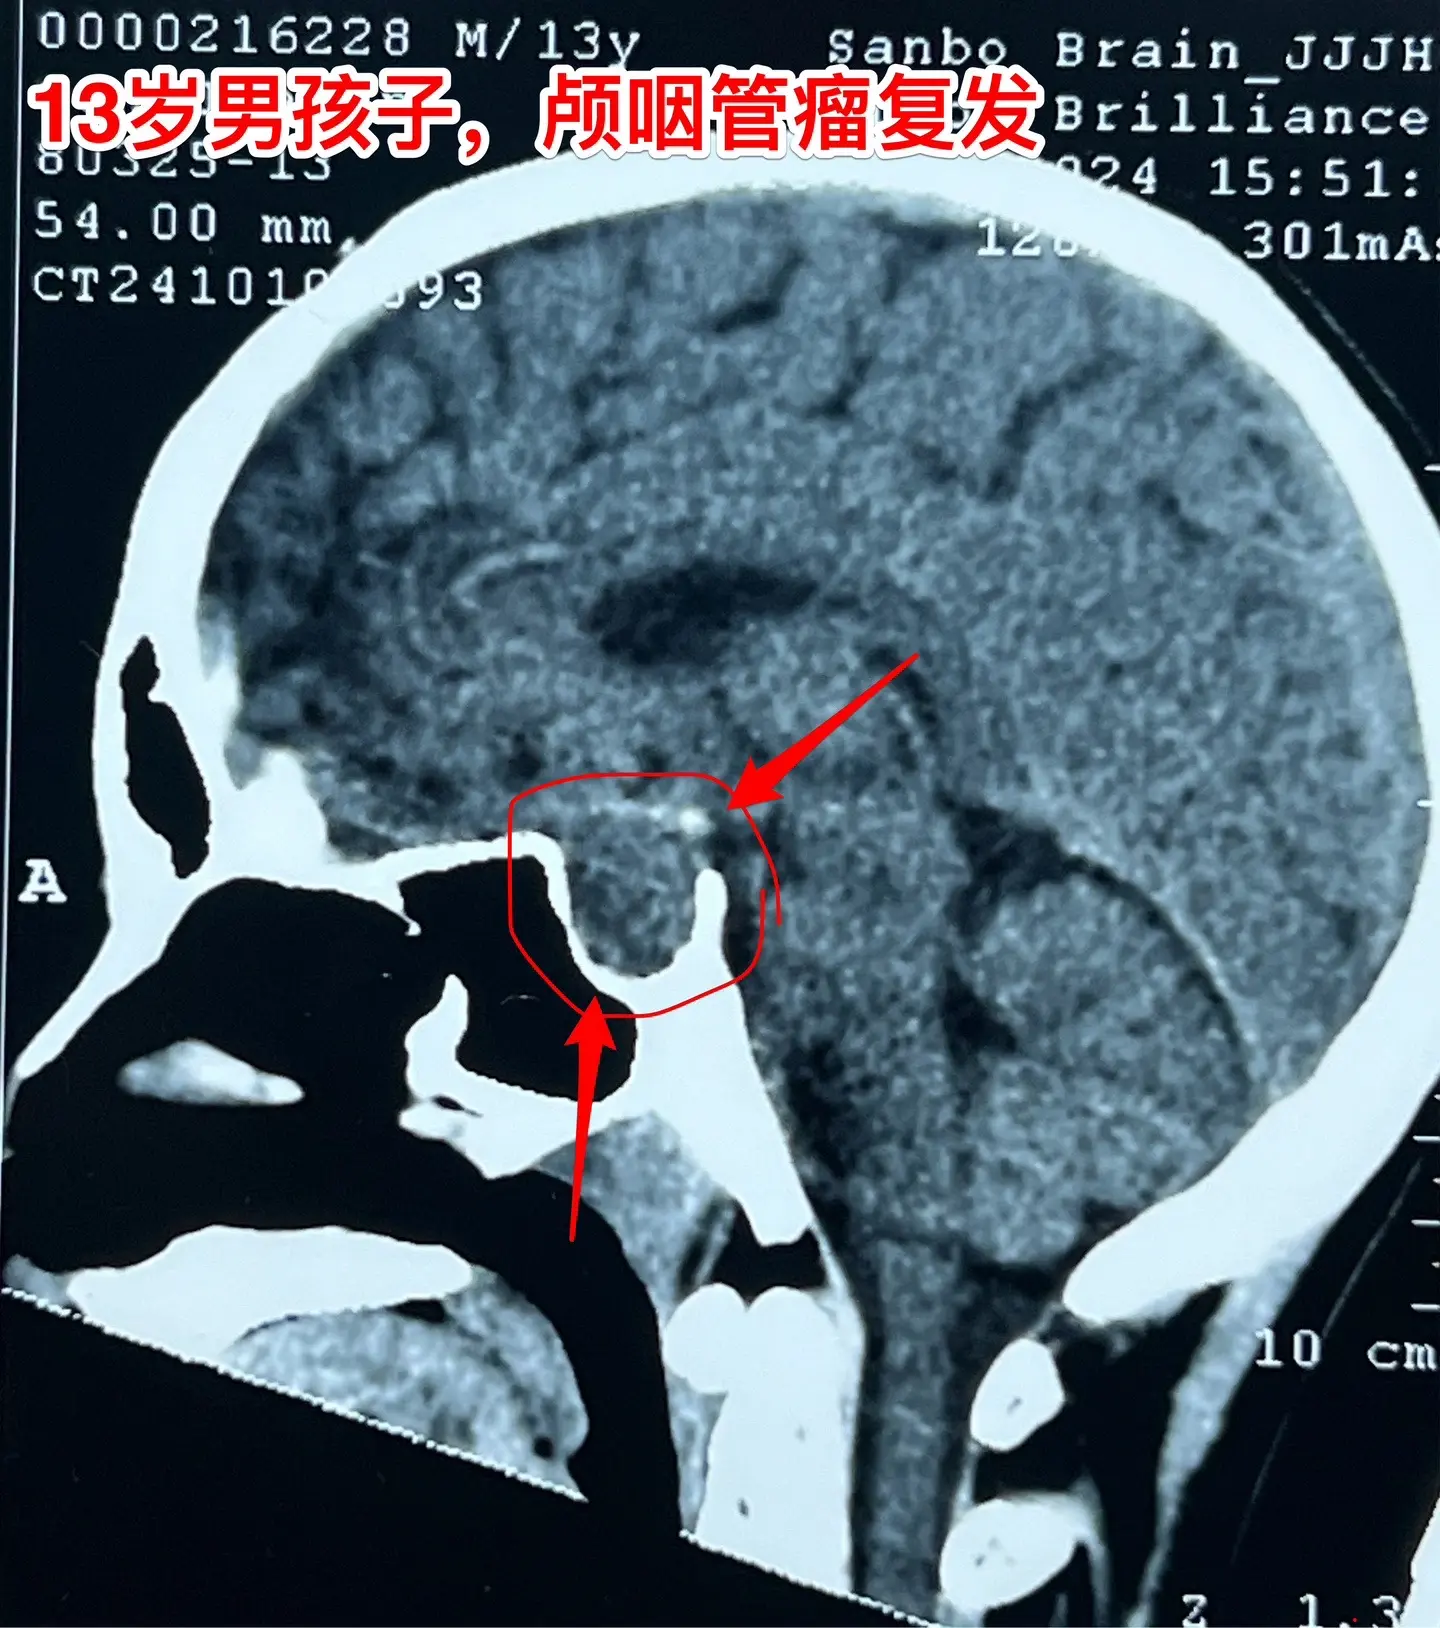

鞍隔下型颅咽管瘤经翼点入路切除合适吗?13岁的山东省菏泽市男孩子,九年前因右眼失明了到医院检查才发现了颅咽管瘤,在外院行手术切除大部分的肿瘤(经翼点入路)。2年前因肿瘤复发在同一个医院再次经原切口切除颅咽管瘤,肿瘤仍未得到完全切除(图3可以看见骨瓣位置)。 肿瘤形态见图,是鞍隔下型的颅咽管瘤。鞍隔下型颅咽管瘤采用翼点入路是很难达到完全切除的,因为垂体窝内的肿瘤处于视觉的死角内,手术医生无法看见。今天(10月20日)我们采用经额底纵裂入路将肿瘤完全切除。手术中意外发现,垂体和垂体柄结构很清晰,得到了保留。 希望肿瘤不再复发。